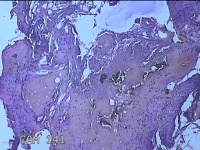

性别

女

年龄

28岁

临床诊断

1.疖肿病 2.皮脂腺囊肿

一般病史

外阴部起丘疹疼痛一周。

标本名称

外阴部包块

大体所见

灰白暗红色包块1x0.7x0.3cm一个,表面糜烂。